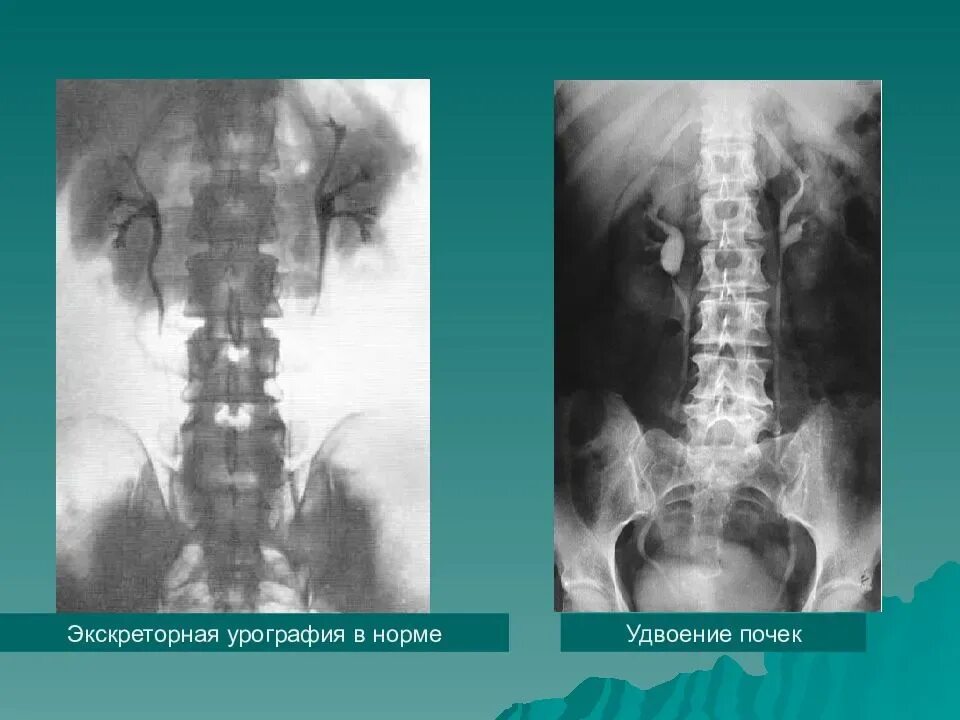

Урография с контрастом